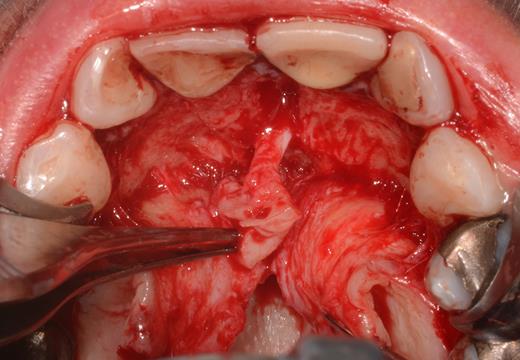

After a sulcular incision on the palatal side from teeth 15 to 25 and an incision in the midline of the palate omitting the incisive papilla and the two orifices of the NPD, two full-thickness mucoperiosteal flaps were raised. Thereafter, the incisive papilla and the whole contents of the incisive canal were enucleated (Figs 4–6). The bony incisive canal was filled with autologous bone harvested from the palatal region (bone scraper) (Fig. 7). A tension-free primary wound closure was achieved by moving the palatal flaps to the midline using single button and interdental vertical mattress sutures (Monocryl 4-0, Ethicon, Johnson & Johnson, USA) (Fig. 8). To avoid wound dehiscence and hematoma, an iodoforme gauze and a palatal plate were applied (Fig. 9). The patient was instructed to rinse three times a day with 0.1% chlorhexidine (formula hospitalis) for 2 weeks postoperatively. Sutures were removed after 14 days.

Preparation of the soft tissue of the incisive canal and the incisive papilla.